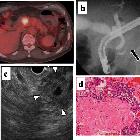

A mixed

adenoneuroendocrine carcinoma of the pancreas: a case report. PET-CT revealed increased accumulation in the mass of the pancreas head (maximum standardized uptake value (SUV max): 5.6 (initial) and 7.8 (delayed) (a). Endoscopic retrograde cholangiopancreatography (ERCP) showed severe narrowing and obstruction of the main pancreatic duct by the tumor (arrow) (b). Endoscopic ultrasonography (EUS) showed the tumor as a low echoic mass (c). Cytological analysis by means of EUS-guided fine-needle aspiration (FNA) suggested a neuroendocrine tumor (G2) (d)